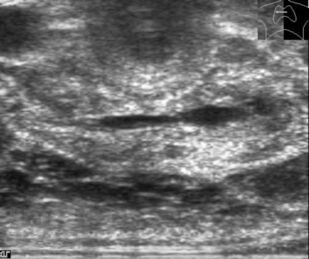

В основу монографии положены материалы собственных исследований и практический опыт использования ультразвуковых методов диагностики при обследовании пациентов после хирургических вмешательств на щитовидной железе. Продемонстрированы диагностические возможности ультразвукового исследования в оценке состояния оперированной щитовидной железы в раннем и отдаленном послеоперационном периоде. Обобщена, систематизирована и представлена ультразвуковая семиотика зоны операции в ближайшие сроки после хирургических вмешательств и отражена динамика выявленных изменений. Убедительно показано, что ультразвуковое исследование может быть эффективным методом послеоперационного наблюдения.